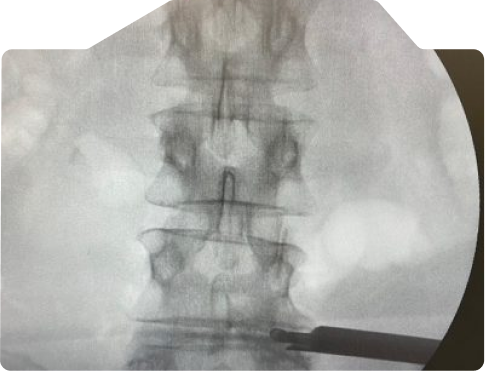

Veja casos de antes e depois dos meus pacientes:

Trata-se de uma técnica que pode ser utilizada em alguns casos para retirada do disco herniado e que a incisão cirúrgica é menor do que 1 cm e o paciente tem alta no mesmo dia da cirurgia com uma recuperação ainda mais rápida.